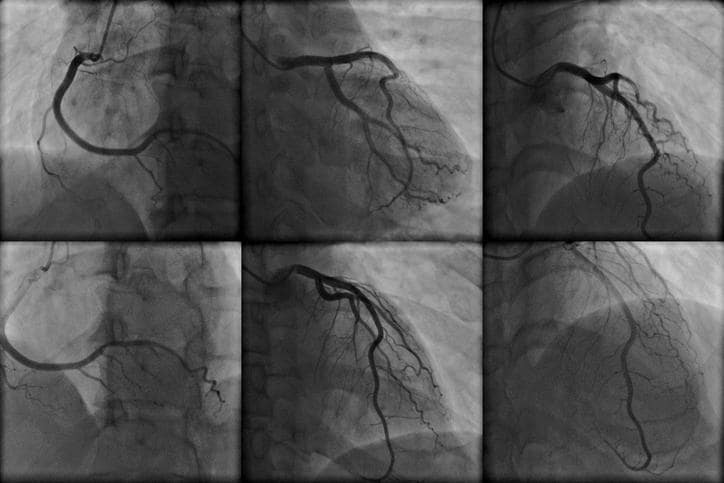

Tutta la procedura è guidata dalle radiazioni ionizzanti (il paziente è disteso su un lettino che emette raggi X), che restituiscono un’immagine (come una semplice radiografia) proiettata su uno schermo, in modo che il radiologo che esegue la procedura possa orientarsi e sospingere il catetere fino a raggiungere la radice dell’aorta. Giunti in corrispondenza dell’ostio coronarico, si inietta il mezzo di contrasto, prima nella coronaria sinistra e successivamente nella coronaria destra.

Con il mezzo di contrasto sarà possibile visualizzare il circolo coronarico, individuando:

- anomalie nel decorso,

- alterazioni anatomiche,

- aree stenotiche, visibili come aree in cui si ha una riduzione del flusso del mezzo di contrasto,

- aree ostruite, visibili come un arresto della progressione del mezzo di contrasto.